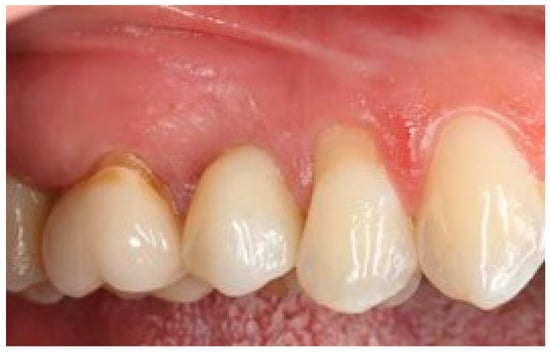

Figure 16.

Five-year follow-up. Element 1.5 of the same patient.

Figure 14 visualizes the mean distance between the soft tissue margin and fixture surface over time, from three months (T1) to 5 years (T3), for both the test and control groups. The error bars represent the standard deviation for each mean value, providing a visual representation of the variability within each group at each time point. At baseline and 3 months, there were no significant differences between the test and control groups (p > 0.05). At 1 year and 5 years, the test group showed significantly smaller distances compared to the control group (p < 0.01 and p < 0.001, respectively). The test group demonstrated a gradual decrease in distance over time, while the control group showed a slight increase. The clinical aspects are shown in Figure 15 and Figure 16.